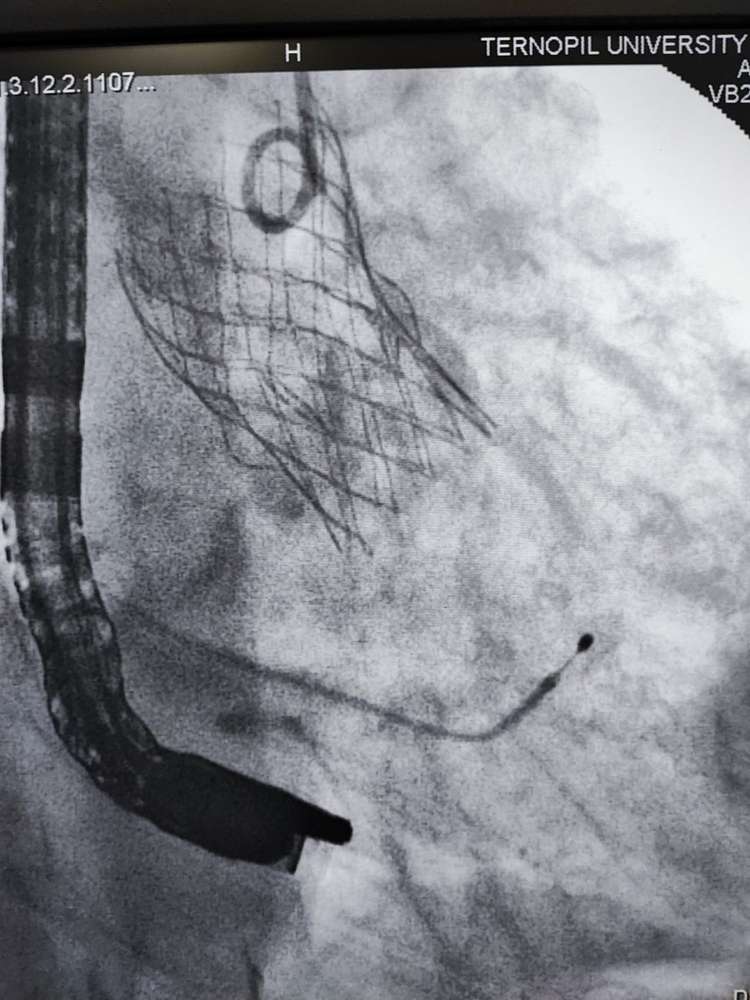

В Тернопільська обласна клінічна лікарня вперше виконано транскатетерну імплантацію аортального клапана через трансапікальний доступ.

Одна з пацієнток має важке викривлення хребта, і внаслідок цього анатомічно складне положення серця, аорти та інших внутрішніх органів, яке практично унеможливлювало виконання заміни клапану іншим доступом окрім трансапікального. Суть операції полягає в тому, що на працюючому серці виконується невеликий отвір, через який через трубку-катетер по провіднику вводиться згорнутий клапан, – йдеться в дописі.

Лікар додає, що позиціонування контролюється як рентгенівським зображенням так і черезстравохідним ультразвуковим датчиком.

Після імплантації хірург затягує вузол навколо отвору і ушиває рану. Крововтрата є мінімальною. Наша лікарня вже має досвід імплантації шести аортальних клапанів через стегнову артерію. А тепер освоїли і цю методику, яка має свої переваги в певній групі пацієнтів,- зазначив Богдан Маслій.